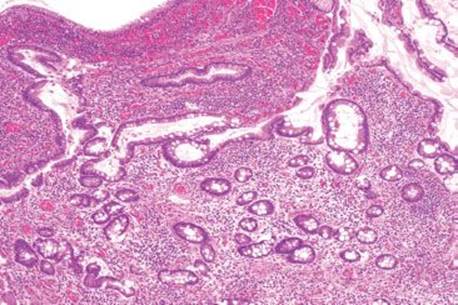

Figure 3.56 Acute ileitis pattern, backwash ileitis, ulcerative colitis. This ileal biopsy was taken from a patient with well-established ulcerative colitis.

Figure 3.57 Acute ileitis pattern, backwash ileitis, ulcerative colitis. Higher magnification of the previous figure reveals mild focal acute inflammation (arrowheads) that should not be mistaken for Crohn disease.

The acute ileitis pattern can also herald inflammatory bowel disease (IBD). Although IBD is discussed at length in Inflammatory Bowel Disease, Chronic Colitis, Colon Chapter, a few comments pertaining to the terminal ileum are warranted. Importantly, terminal ileal injury is not restricted to Crohn disease. Up to 17% of ulcerative colitis cases are associated with acute ileitis via a process termed “backwash ileitis.”12 “Backwash ileitis” occurs in a background of marked pancolitis whereby the inflammatory rich luminal contents in the colon are refluxed into the contiguous terminal ileum segment, causing associated inflammatory and reactive changes. The degree of terminal ileum injury is usually mild, or no greater than that in the cecum, and features of chronic mucosal injury are uncommon (Figs. 3.56 and 3.57).12 If terminal ileum restricted injury is present and the adjoining colon shows unremarkable mucosa, medication injury, infection, or Crohn disease would figure a more likely etiology.